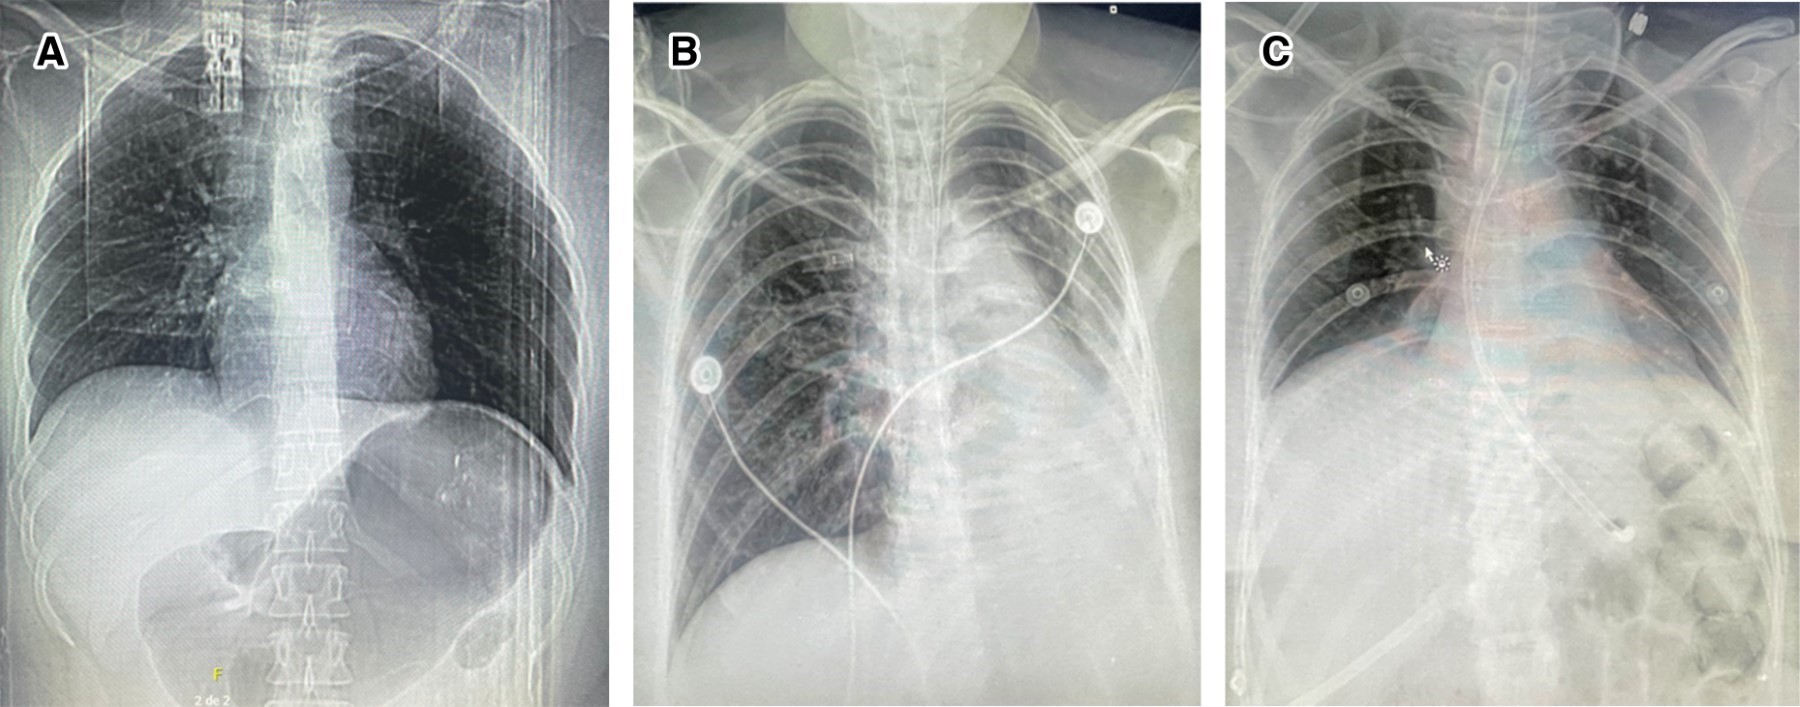

Evolución: a las 24 horas de inicio del sedante inhalado se decidió suspender el bloqueador neuromuscular debido a la mejoría clínica. Cabe señalar que, durante las primeras 48 horas de estancia en la UCI, la paciente empezó a desarrollar datos de lesión renal aguda oligúrica, por lo que requirió manejo con diurético de asa. Debido a la mejoría clínica, se decidió realizar protocolo de retiro de ventilación mecánica con predictores positivos para tolerancia (NIF 40 cmH2O, P0.1 – 4.1 cmH2O, pico flujo 60 L/min, índice de Tobin 20) extubándose con éxito a las 36 horas de haber iniciado la sedación inhalada, y logrando su egreso de la UCI a los 10 días de estancia en la misma, para continuar manejo hospitalario por Medicina Interna con antibióticos y agonista β-adrenérgico de acción larga. Finalmente, fue egresada a casa a los 13 días de estancia hospitalaria con cita para seguimiento por neumología. En la Figura 2 se pueden observar las radiografías de la paciente.

Figura 2